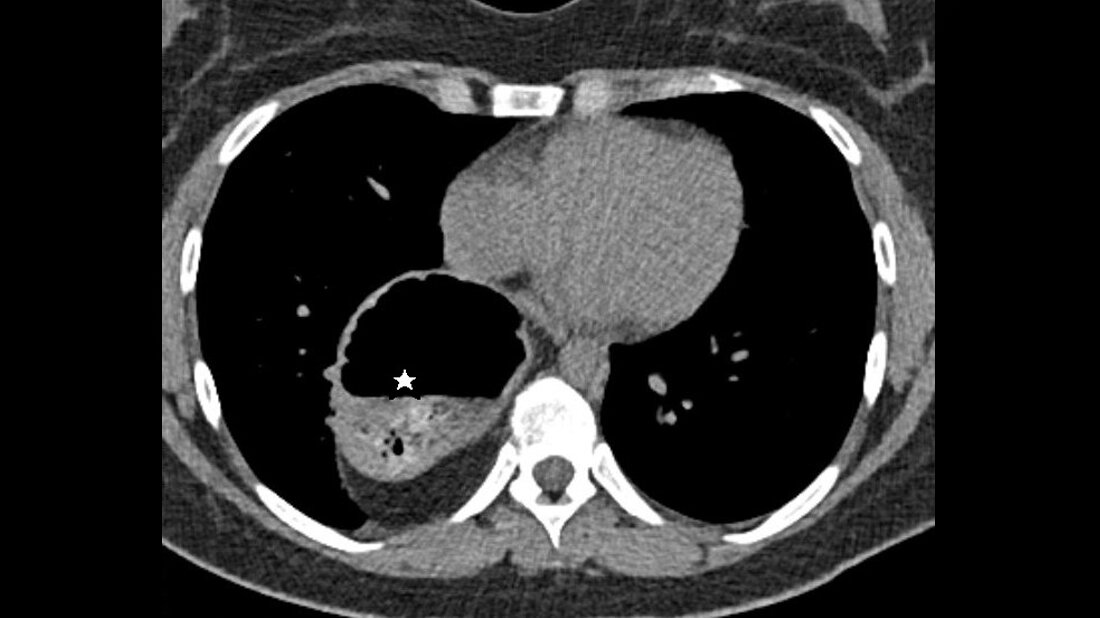

Anomalien und Normvarianten: Interne Veränderungen 2.16 – Intrathorakale Magen-Darm-Luxation

Bei Patienten mit bekanntem abdominellen Trauma sollte immer an die Möglichkeit einer diaphragmatischen Hernie gedacht werden. Der kindliche kongenitale Thoraxmagen ist eine seltene pädiatrische Diagnose.

In patients with a known history of abdominal trauma doctors should be aware of the possibility of diaphragmatic hernia. Congenital intrathoracic stomach is an uncommon pediatric diagnosis.